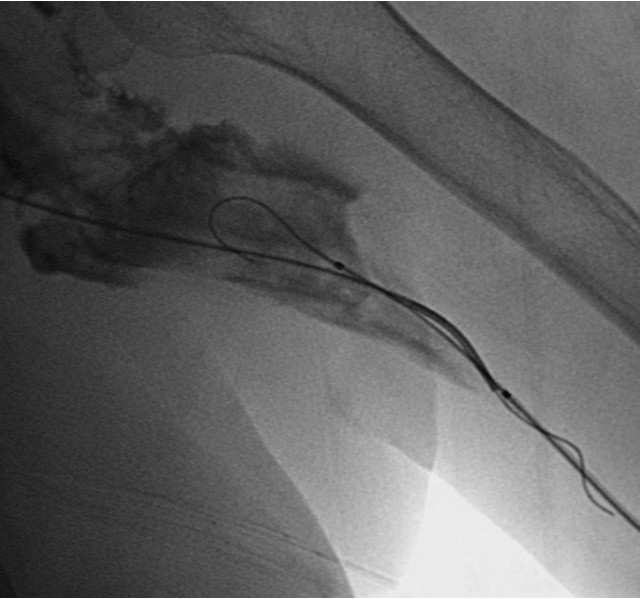

환자의 AV fistula는 초음파상 total thrombotic occlusion 된 상태였으며 시술 전 urokinase 100000 unit를 사용하여 thrombolysis and aspirated thrombectomy를 시행하였다. 그 후 시행한 shuntogram(Fig. 1) 상 left basilic vein 의 total ocdusion을 보이며 초음파상 remant vein의 크기는 1mm 이하로 확인되었다. 투시하에서 확인되는 outflow vein은 없었기에 초음파 유도하에 5 Fr Kumpe catheter(Soft-Vu, AngioDynamics, USA, NY) 에 0.035’ straight-tip guide wire(Terumo, Tokyo, Japan)를 사용하여 막힌 left basilic vein으로 15cm 이상 진행하였으며(Fig. 3), 4mm balloon (synergy, Boston, Ireland)를 사용하여 blind angioplasty를 하며 true lumen으로의 진행을 시도하였으나 실패하였다(Fig. 4). 더 이상의 antegrade로의 접근은 어려울 것으로 판단하여 regrograde approach를 위하여 left internal jugular vein 을 초음파 유도하에 9Fr sheath( Accu-Sheath, Sungwonmedical, Korea, Cheongju)을 사용하여 access 하였다. (Fig. 5A) 그리고 5Fr Cobra & sherpherd hook catheter (A&A M.D., Korea, Sungnam) 를 이용하여 left axillary vein으로의 접근을 시도하였다(Fig. 5B).

Fig. 3.

A-B. Guide wire negotiation into occluded left basilic vein with 4mm balloon